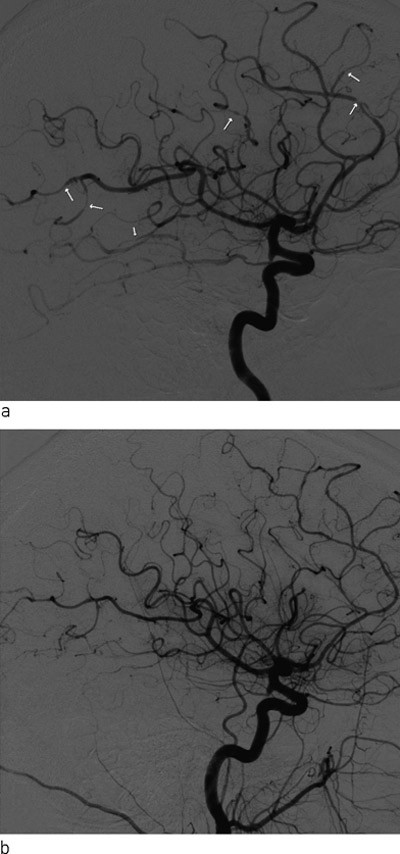

På mistanke om subaraknoidalblødning ble det rekvirert CT caput. På denne var det tegn til subaraknoidalt blod beliggende over konveksitetene langs gyri på begge sidene av falx cerebri. Differensialdiagnostisk kunne det dreie seg om eksudasjon av proteinrik væske. Det ble deretter utført MR cerebrum med arteriell og venøs angiografi, som viste multippel sklerose-forandringer, som ved tidligere undersøkelser, samt subaraknoidalt blod som beskrevet. Aneurismer eller karmisdannelser ble ikke påvist. I figur 1 er CT- og MR-funnene vist. Spinalvæskeanalyse 12 timer senere viste rikelig med erytrocytter, men fravær av bilirubin. Proteinverdien og leukocyttallet i spinalvæsken var lett forhøyet, henholdsvis 875 mg/l og 6 · 10⁶/l, noe som også kunne forklares av multippel sklerose.

Sykehistorien, kliniske funn, CT- og MR-bilder var altså forenlig med subaraknoidalblødning, men noe åpenbart blødningsfokus kunne ikke påvises. Den symmetriske lokaliseringen av blodet over konveksitetene på begge sider av falx cerebri var også uvanlig.